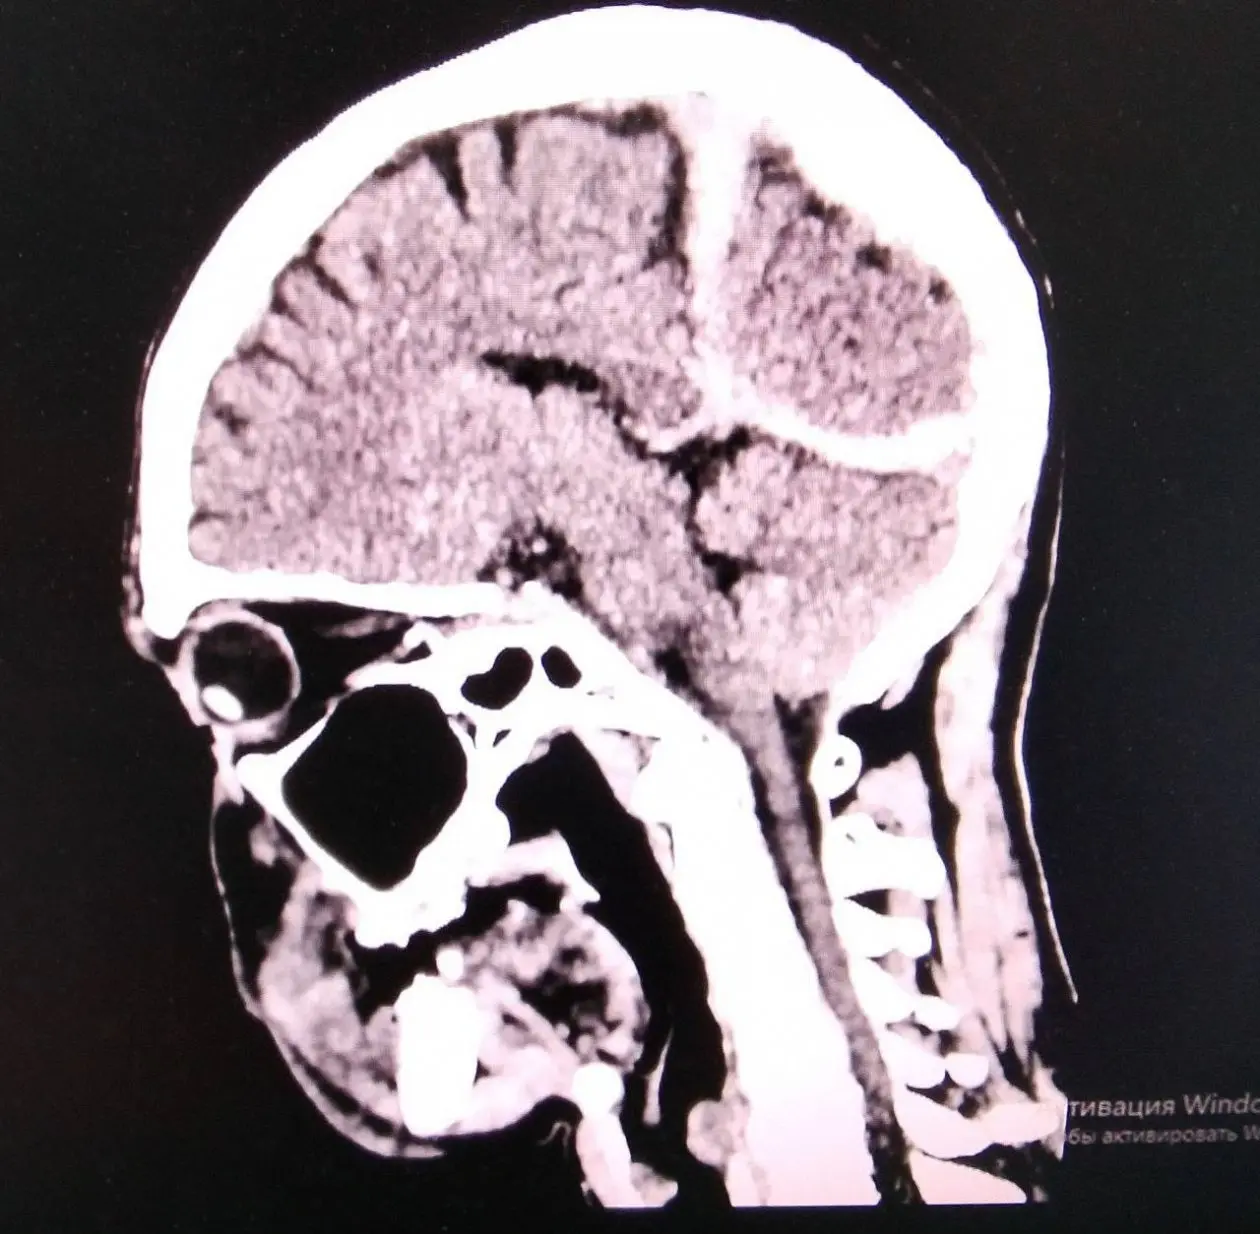

Снимок головы. Фото: Пресс-служба Минздрава Приморья

Обследование показало, что у пациента была субдуральная гематома, ушиб головного мозга и рана головы. Пострадавшего обнаружили местные жители, после чего его доставили в больницу.